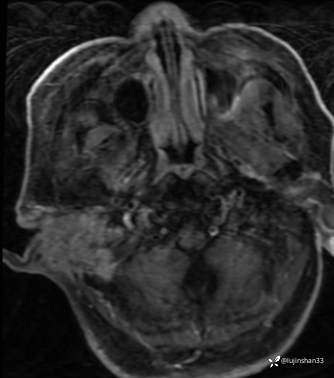

简要病史:患者2022年10月掏耳后出现右耳疼痛,流水,伴血性分泌物,伴听力下降,无头痛头晕,无口角歪斜,自行购买滴耳液及口服罗红霉素,效果不佳。后右耳痛加剧,偶需止疼药治疗。后于XXXXXX医院行中耳乳突CT检查示“右耳恶性肿瘤?坏死性外耳道炎?”颅脑磁共振平扫示“脑内多发缺血灶、梗塞灶,脑白质疏松,脑萎缩、右中耳恶性占位。”建议上级医院治疗。2023-4-13就诊于我科门诊,行右外耳道病理活检示“鳞状上皮黏膜慢性炎伴急性炎,可见较多炎性坏死,部分上皮增生明显伴不典型增生,小灶上皮呈重度异型增生伴癌变。”建议手术治疗。今患者为求进一步诊治,门诊以“颞骨占位(右)“收治入院。

MRI:

右侧颞骨鳞癌(T4)